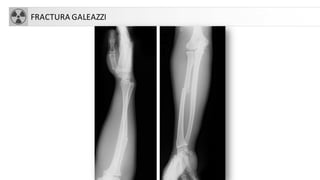

• Fx Galeazzi: Fx diáfisis radial + Luxación radioulnar distal

FRACTURA GALEAZZI